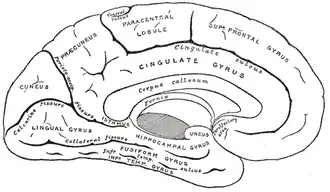

С неврологическим субстратом репереживаний связаны несколько участков головного мозга. Наиболее часто с расположением непроизвольных воспоминаний связывают медиальные височные доли, предклинье, заднюю поясную извилину, переднюю лобную кору (см. Кора больших полушарий)[14].

Обычно с памятью связывают медиальные височные доли[15]. Более конкретно, они связаны с эпизодической (описывающей) памятью, следовательно, их нарушение ведёт к сбоям в её работе[15]. Гиппокамп, размещённый в участке медиальных височных долей, тоже тесно связан с процессами памяти[15]. Он имеет множество функций; они также включают аспекты объединения памяти[15]. Исследования по нейровизуализации показали, что психопатологические репереживания активируют участки, связанные с возвращениями воспоминаний[14]. Предклинье, размещённое в верхней теменной доле, и задняя поясная извилина также вовлечены в эти процессы[14]. Кроме того, исследования показали при репереживаниях активность в участках префронтальной коры[14].

Таким образом, медиальные височные доли, предклинье, верхняя теменная доля и задняя поясная извилина связаны с психопатологическими репереживаниями согласно их ролям в восстановлении памяти.